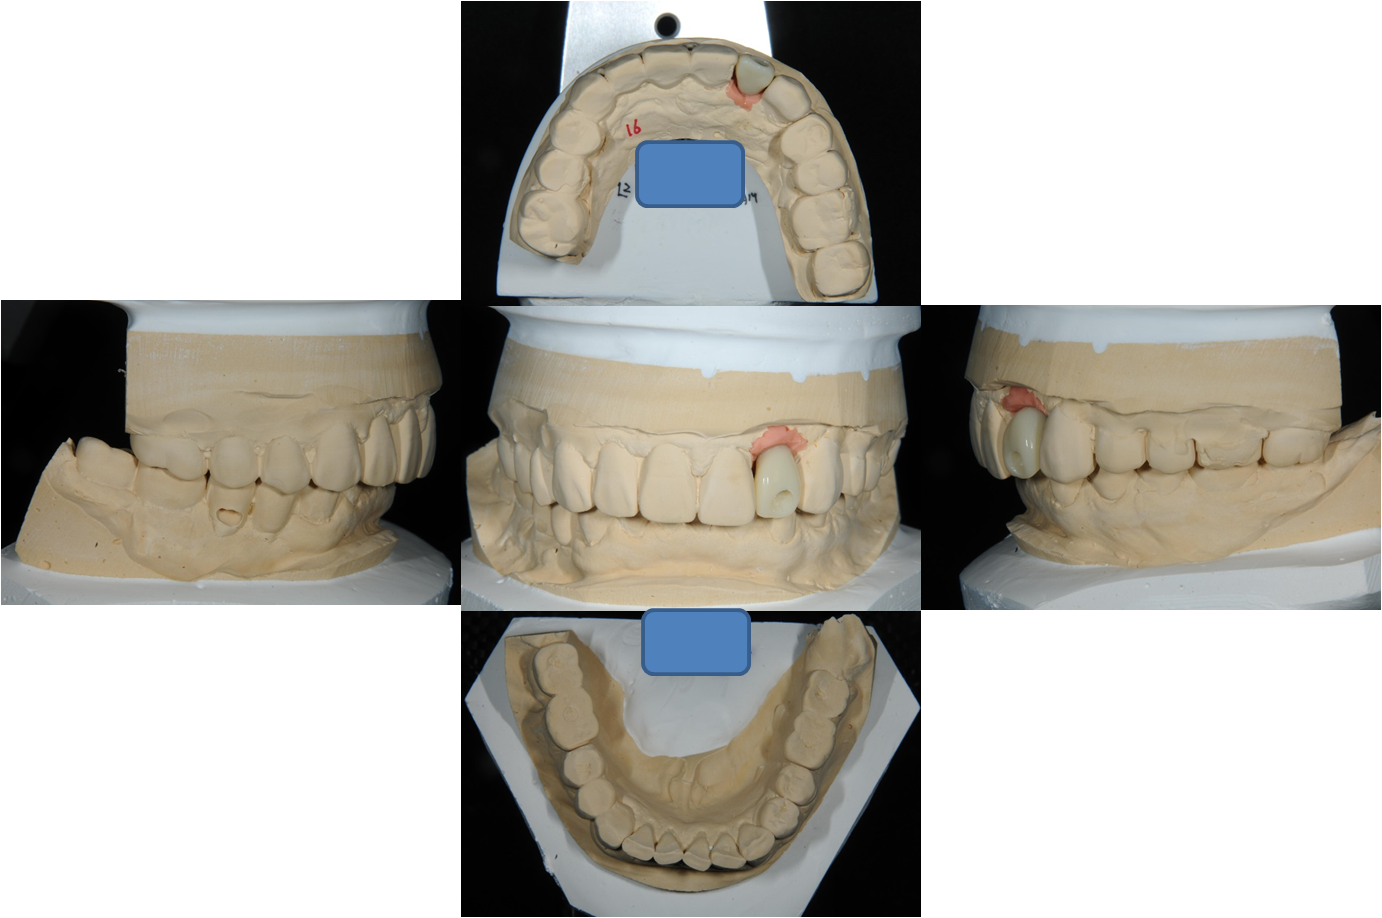

印模上咬合器

模型製作

臨時假牙塑形

塑形後再印模